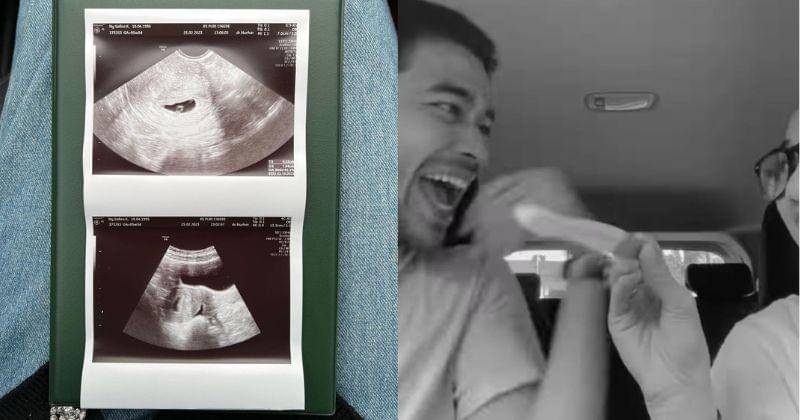

3. Diprediksi lahir pada bulan Oktober 2023

Melalui foto ultrasound yang dibagikan, kandungan Safira saat ini sudah memasuki trimester pertamanya. Pada foto tersebut terlihat pula hari perkiraan lahir untuk anak pertama pasangan baru ini.

Tertulis 23 Oktober 2023 akan menjadi hari kelahiran si calon bayi. Jika benar demikian, maka bayi pertama Wafda dan Safira akan lahir di tanggal yang cantik karena memiliki deretan angka 23.10.23.